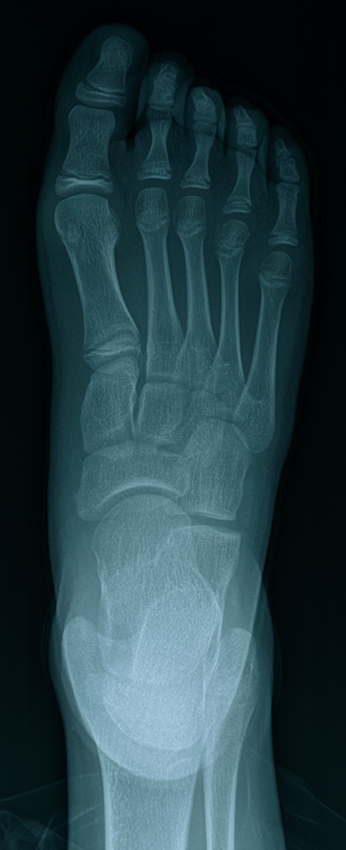

The boy wanted to be an American Ninja Warrior.”I can scale this wall”, he says to himself. He takes off, mindful of the debris under his feet, gravel, bottle caps, branches. A small pile of wet leaves in front of the wall, located just where he would push off and leap to begin his rapid ascent thwarts him. He slips, slides and bangs his right foot into the wall. A Sunday in bed, ice and Tylenol. A Monday at the hospital, x-rays, a 3 week boot. Lost youth.